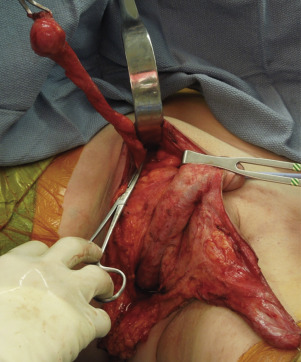

Following elevation of both the penile and the scrotoperineal flaps, access to the testicles and spermatic cords is established, allowing the performance of bilateral orchiectomies. The orchiectomies, including resection of the spermatic cords, are carried out at the level of the external inguinal ring ( Figs. 5.11 and 5.12 ). Resection of the spermatic cord at this level allows the spermatic cord to retract within the inguinal canal and prevents a palpable bulge in the groin area. The skin of the penile shaft is then circumferentially incised at the junction of the glans and penile shaft, facilitating elevation of the penile flap ( Fig. 5.13 ). This facilitates separation of the penile skin from the underlying corpora cavernosa and corpora spongiosum, as well as the underlying muscles, the ischiocavernosus and bulbospongiosus muscles, respectively ( Fig. 5.14 ).